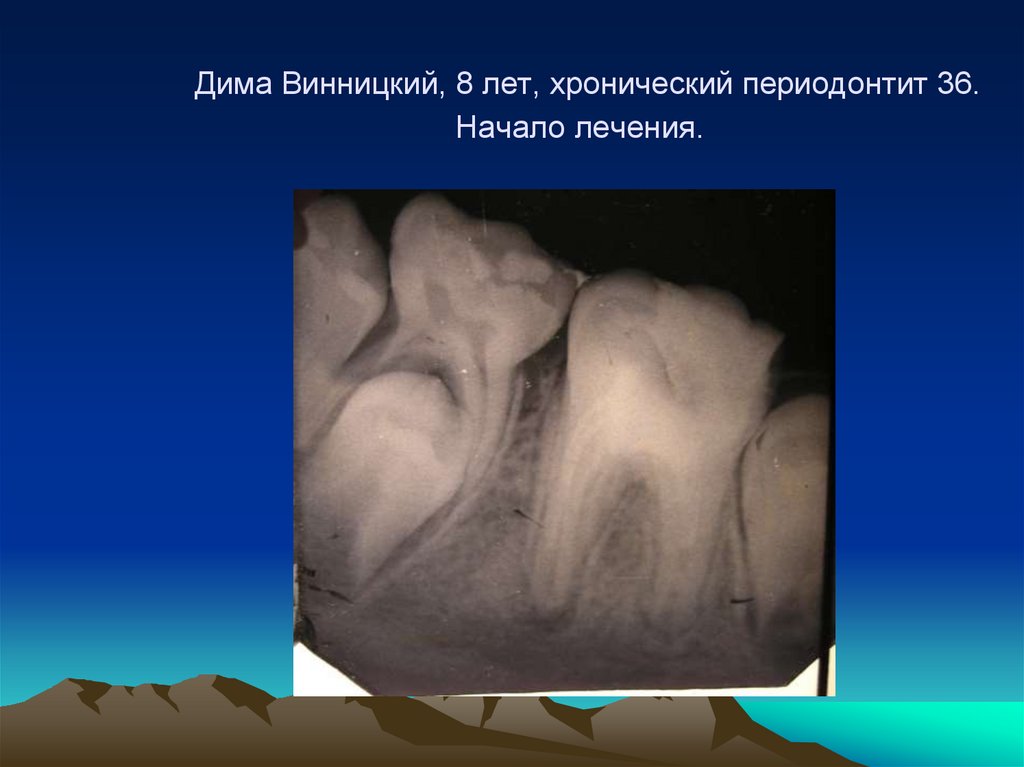

Дима Винницкий, 8 лет, хронический периодонтит 36. Начало лечения.

89. Дима Винницкий, 8 лет, хронический периодонтит 36. Начало лечения.